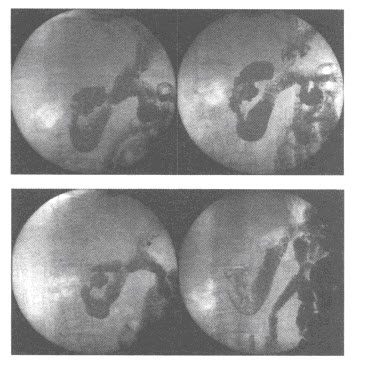

161、多项选择题

男,24岁,鼻部被击伤,如图所示,最可能的诊断是()

A.鼻骨中段见透亮线影

B.鼻骨远端稍塌陷

C.鼻骨骨折处可见小骨片影向下方分离

D.考虑为鼻骨线性骨折

E.鼻骨粉碎性骨折